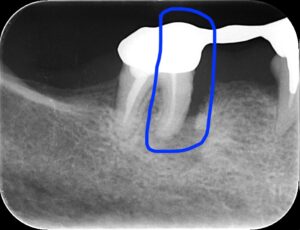

画像のレントゲンでは青線で囲った部分の骨が溶け

膿が溜まっています。

そのため青で囲った部分の抜歯が必要になります。

これをヘミセクションと言います。

青線部が腫れている部分です。